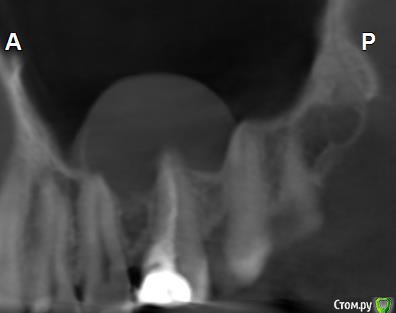

Здравствуйте! Верхний правый шестой зуб пломбировали 3 месяца назад. Примерно месяц назад он начал ныть, после насморка, сначала периодами, а теперь почти постоянно. При постукивание (ощущается не совсем так, как другие зубы) и пальпации десны он не болит. 2,5 месяца назад удаляли кисту из гайморовой пазухи. Может ли быть это какое-то воспаление и есть ли вероятность устранить его какими-нибудь антибиотиками, если да, то как, или может удалить зуб? Если есть воспаление, то какие могут быть последствия если не удалить зуб?

(Снимки с КТ, первые 8(Image) - сделаны сейчас,по 4 в разных проекциях, вторые 8(Before) - сделаны 5 месяцев назад до удаление кисты и повторного пломбирование зуба( до повторного пломбирование он реагировал на горячее, был запломбирован 3 года))